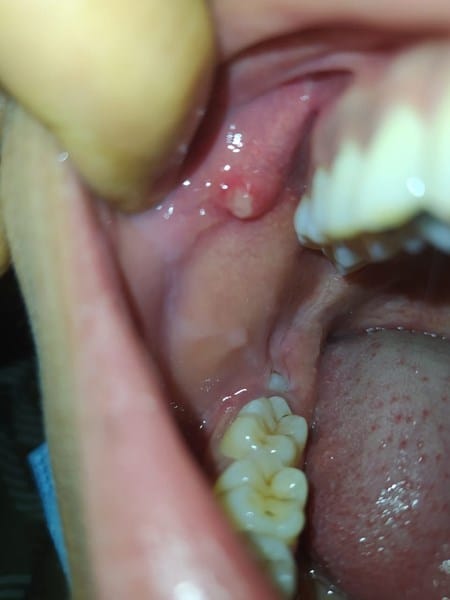

Hace unos días me salio una protuberancia que duele un poco en la mejilla quisiera saber que desde otro punto de vista

Tengo dos protuberancias iguales de los dos lados solo que la de el lado derecho esta inflamada y me duele eh leido y las protuberancias pueden ser el conducto de stenon es verdad? Y me gustaria saber porque una esta inflamada y duele

Me pasa igual amigo que el de la foto - Droc Baa